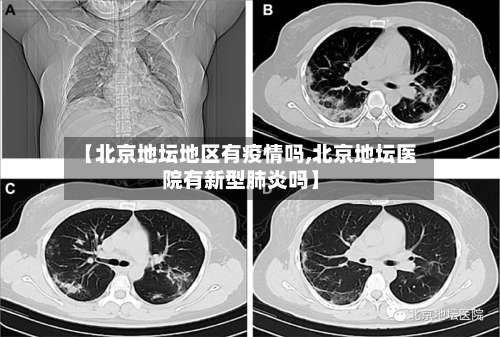

〖壹〗、北京地坛医院一个确诊妈妈诞下新生儿 ,这个新生儿她并没有患有新冠,病毒经过接生之后将这个小孩子放在了封闭的一个区域内,也就让医护人员每天去检查他的身体以及帮他做一些咽拭子 ,在隔离了14天之后,发现证明孩子状况良好,没有患有新冠病毒 。

〖贰〗 、北京有一位即将生产的孕妇 ,而且这名孕妇是新冠病毒感染者,4月29日这名孕妇作为确诊病例转到了北京地坛医院,孕妇已经妊娠39周五天 ,随时都有可能会分娩,这名患者入院后引起了院内的高度关注,地坛医院的专家和市级专家一起制定了分娩方案。